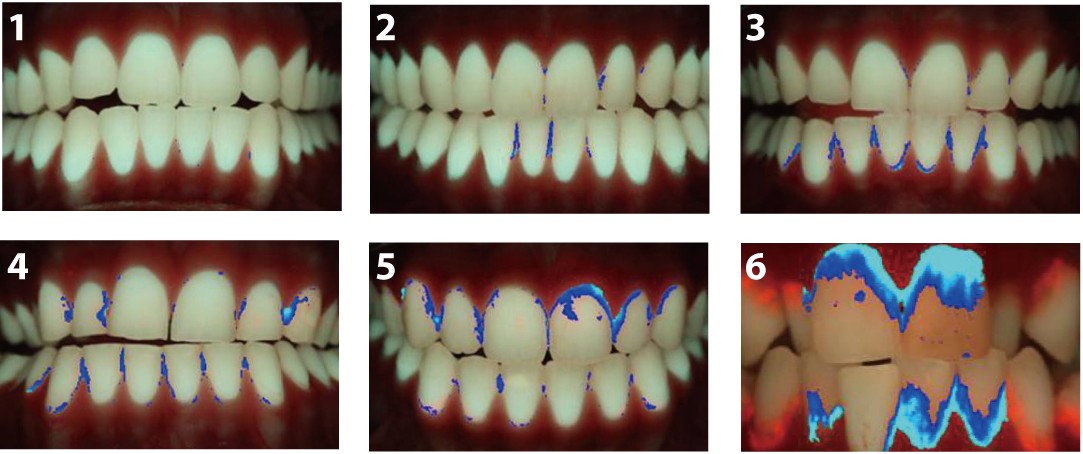

QLF-D분석프로그램(QA2)

C3프로그램을 통해 저장된 이미지를 분석하여 구강 내 상태의 세균분포정도를 정량적 정성적으로 분석하는 시스템으로 치태염색제를 사용하지 않고 간단한 촬영만으로 3일이상된 세균을 영상으로 파악할 수 있으며, 이를 자동으로 점수화 할 수 있습니다.